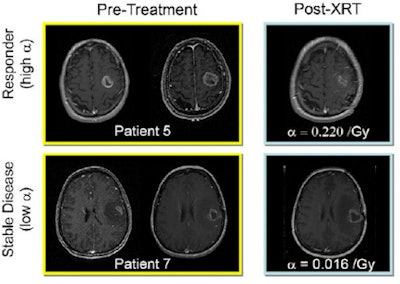

| Response to therapy is conventionally assessed by determining changes in gross tumor volume on MRI prior to and after the administration of therapy. Postcontrast T1-weighted MRI images are shown for two glioblastoma patients who would typically be separated into generic groups: responder and stable disease. The radiation response parameter α gives an additional quantification of radiation response for each patient. Image courtesy of Physics in Medicine and Biology. |

The enhanced model was tested on nine histologically diagnosed glioblastoma patients. All patients underwent at least two pretreatment and one post-therapy MRI exam (postcontrast T1-weighted [T1Gd] and T2-weighted). Tumor growth velocity was estimated from the change in tumor radius between two pretreatment MR images (spaced by a minimum of five days). This growth velocity, together with a tumor cell gradient inferred by comparing the T1Gd and T2 images, was used to calculate proliferation and invasion values for each patient -- thus uniquely characterizing that glioma's untreated growth kinetics.

The MRI-derived parameters were used to create a virtual tumor for each patient, which was then "treated" with the same radiation dose and fractionated radiotherapy plan as clinically prescribed. To estimate the parameter α for each patient, the researchers simulated radiotherapy using a range of α values. The difference between simulated and observed tumor radii (at the first post-treatment MRI) was recorded and data regression performed to yield a value of α that minimized this difference.